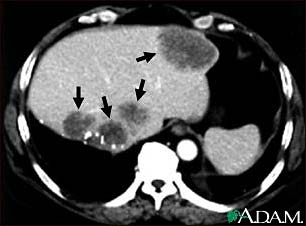

Liver metastases, CT scan

A CT scan of the upper abdomen showing multiple metastasis (cancer that has spread) in the liver of a patient with carcinoma of the large bowel. Note the dark areas in the liver (left side and center of picture).